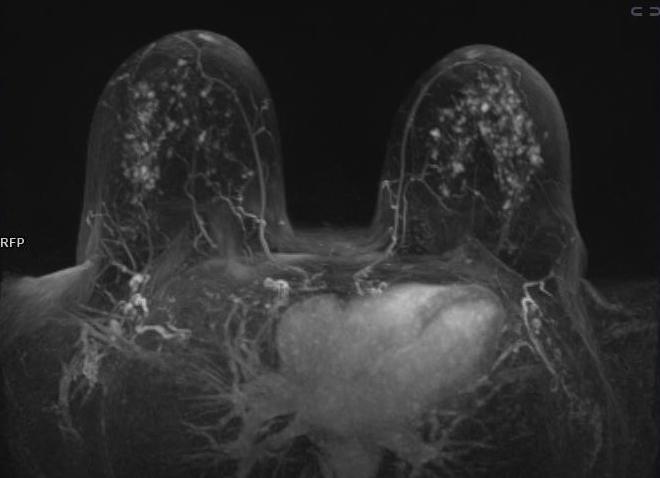

Мрт молочной железы с контрастированием

МРТ молочных желез

МРТ молочных желез проводится чаще всего для выявления различных новообразований в них, а также для диагностики патологии в этой части тела. Использование этого метода позволяет установить достоверный диагноз даже в спорных случаях.